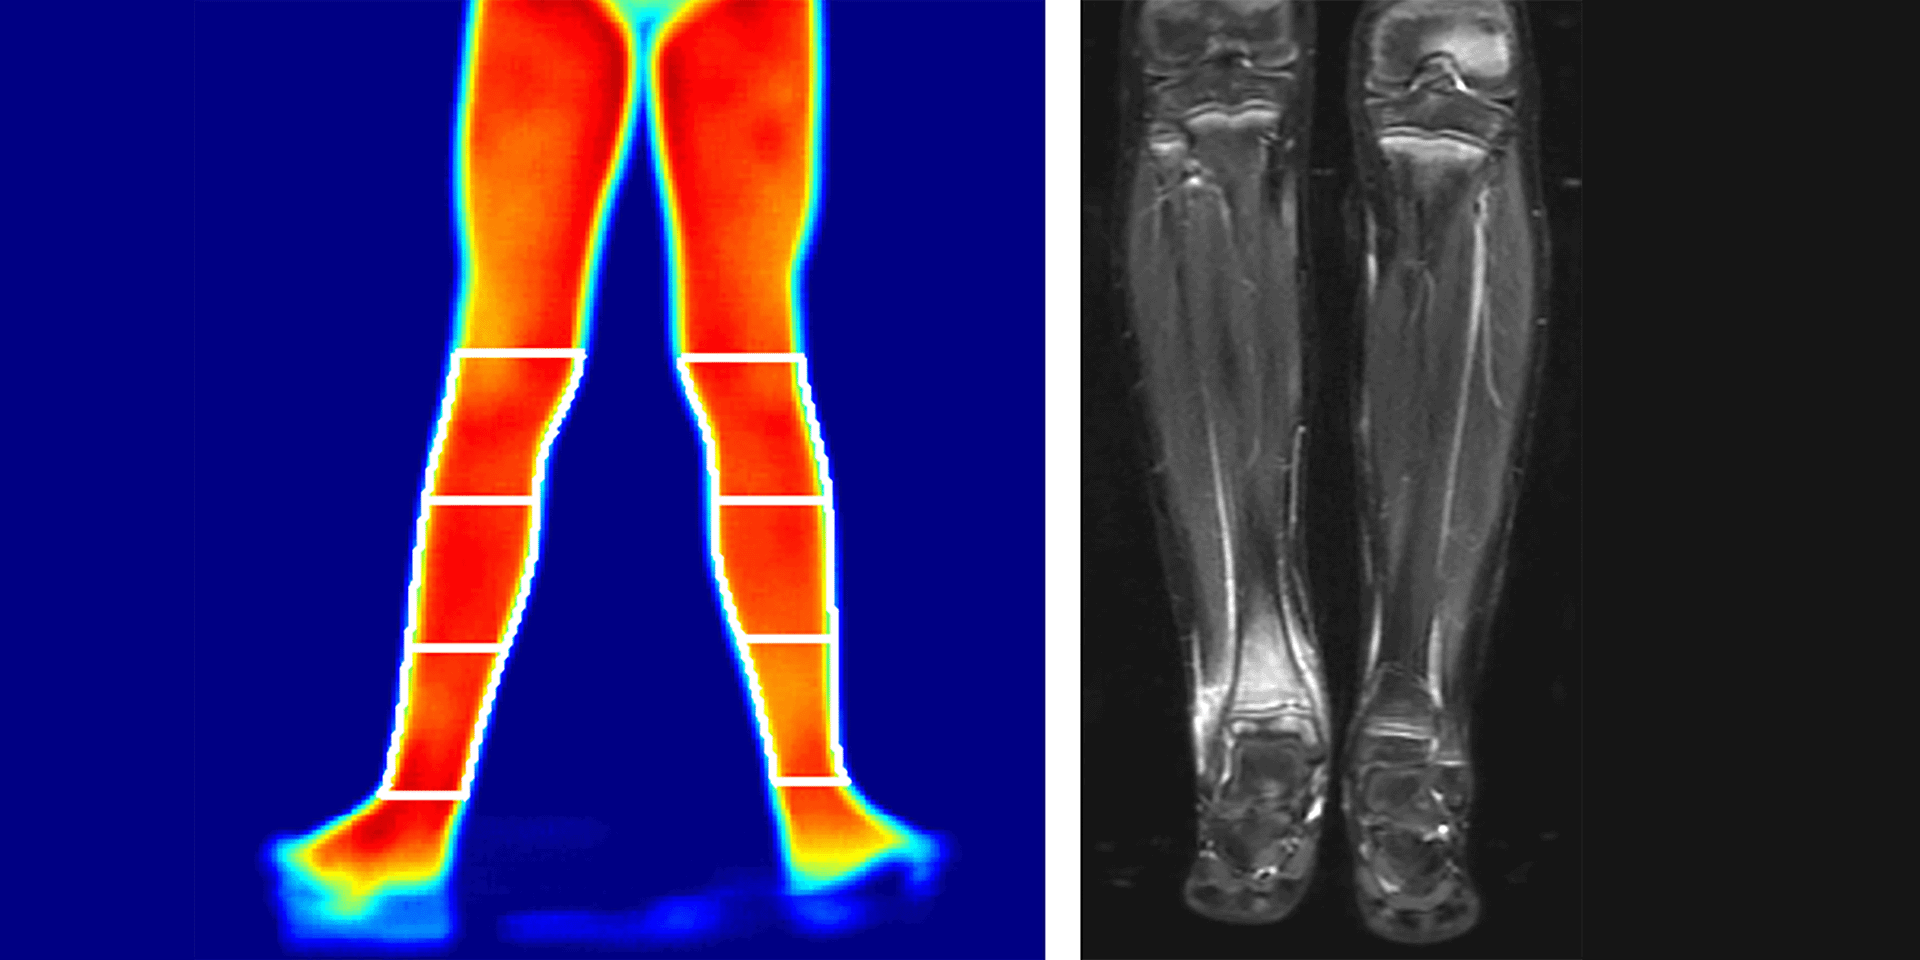

Vishya Adipudi is a senior at the University of Washington studying public health and biochemistry. She contributes to the machine learning and deep learning projects for CRMO imaging. Outside the lab, you can find her hiking, backpacking, camping, volunteering locally, biking and finding Seattle’s best latte.

Daniel Chen works on healthcare AI projects, focusing on CRMO research. Research interests include data wrangling, clustering, computer vision, statistical modeling, multimodal data integration and advanced deep learning architectures such as CNNs, transformers, etc. He also contributes to grant writing and publications. Outside of work, he enjoys hiking, exercising, cooking and exploring new cuisines, parks, botanical gardens and zoos.

Avril Wilson is a recent graduate of the University of Washington with a BS in earth and space sciences, concentrating in biology, and is now going into her first year of the University of Washington MPH program in epidemiology. At Seattle Children's, she is currently working on a project led by Daniel Chen working with CNO imaging and machine learning. Outside of the lab, she is a D1 track and field athlete, as well as a biology tutor and owner of an albino corn snake.